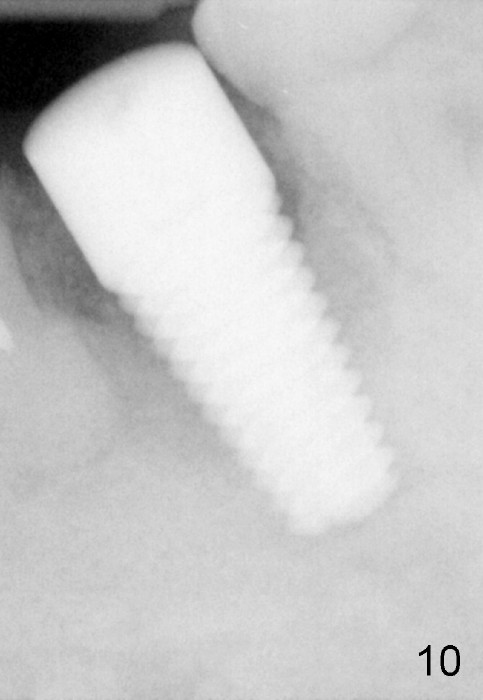

Three months postop, the buccal fistula disappear (Fig.11).  But the implant has mild mobility, as evidenced by a narrow band of radiolucency immediately around the apical portion of the implant (Fig.10).